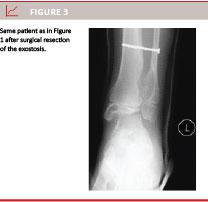

OC is the most common benign bone tumour [1-16] and consists of osseous tissues covered with hyaline cartilage and continuous periost. Usually, OC grows from the metaphysis of the long bones and can be either broad-based or stalky. OCs vary in size from two to twelve centimetres in diameter, and the most common site of involvement is the distal femur, proximal tibia and fibula, both bones of the lower arm and the ankle joint (Figure 1) [3].

MCE is caused by a mutation in the family of tumour suppressor genes called exostotin (EXT), especially mutations in chromosome 8 (EXT1), 11 (EXT2) and 19 (EXT3), and is dominantly inherited (Figure 1 and Figure 2) [8]. The EXT1 and EXT2 mutations change the function of the glycoprotein glycosyltranferase. This protein is responsible for correct cellular growth, differentiation, movement and adhesion of the cell [6]. The pathology of EXT3 mutations is unknown and accounts for a small amount of the patients [8].